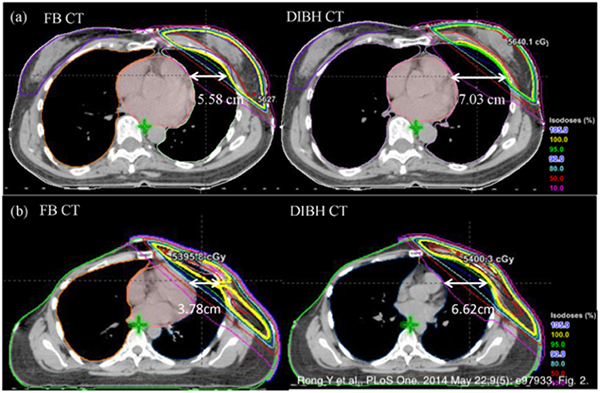

4.ひだり乳房深吸気息止め照射(DIBH) 〜ひだり乳がんの治療で「心臓を守る」〜

ひだり乳がんの放射線治療では、心臓被ばくにより治療後数年から心血管疾患発症リスクが増加するとの研究報告があります。そのため、深く息を吸って心臓を遠ざけた状態(Deep Inspiration Breath Hold)での放射線照射も可能になります。

DIBH治療計画